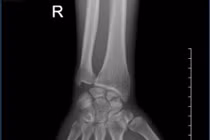

Lấy xương chậu ghép vào cánh tay điều trị khớp giả

Khớp giả là tình trạng xương không liền sau phẫu thuật. Điều trị khớp giả là một quá trình khó khăn, phức tạp và lâu dài.